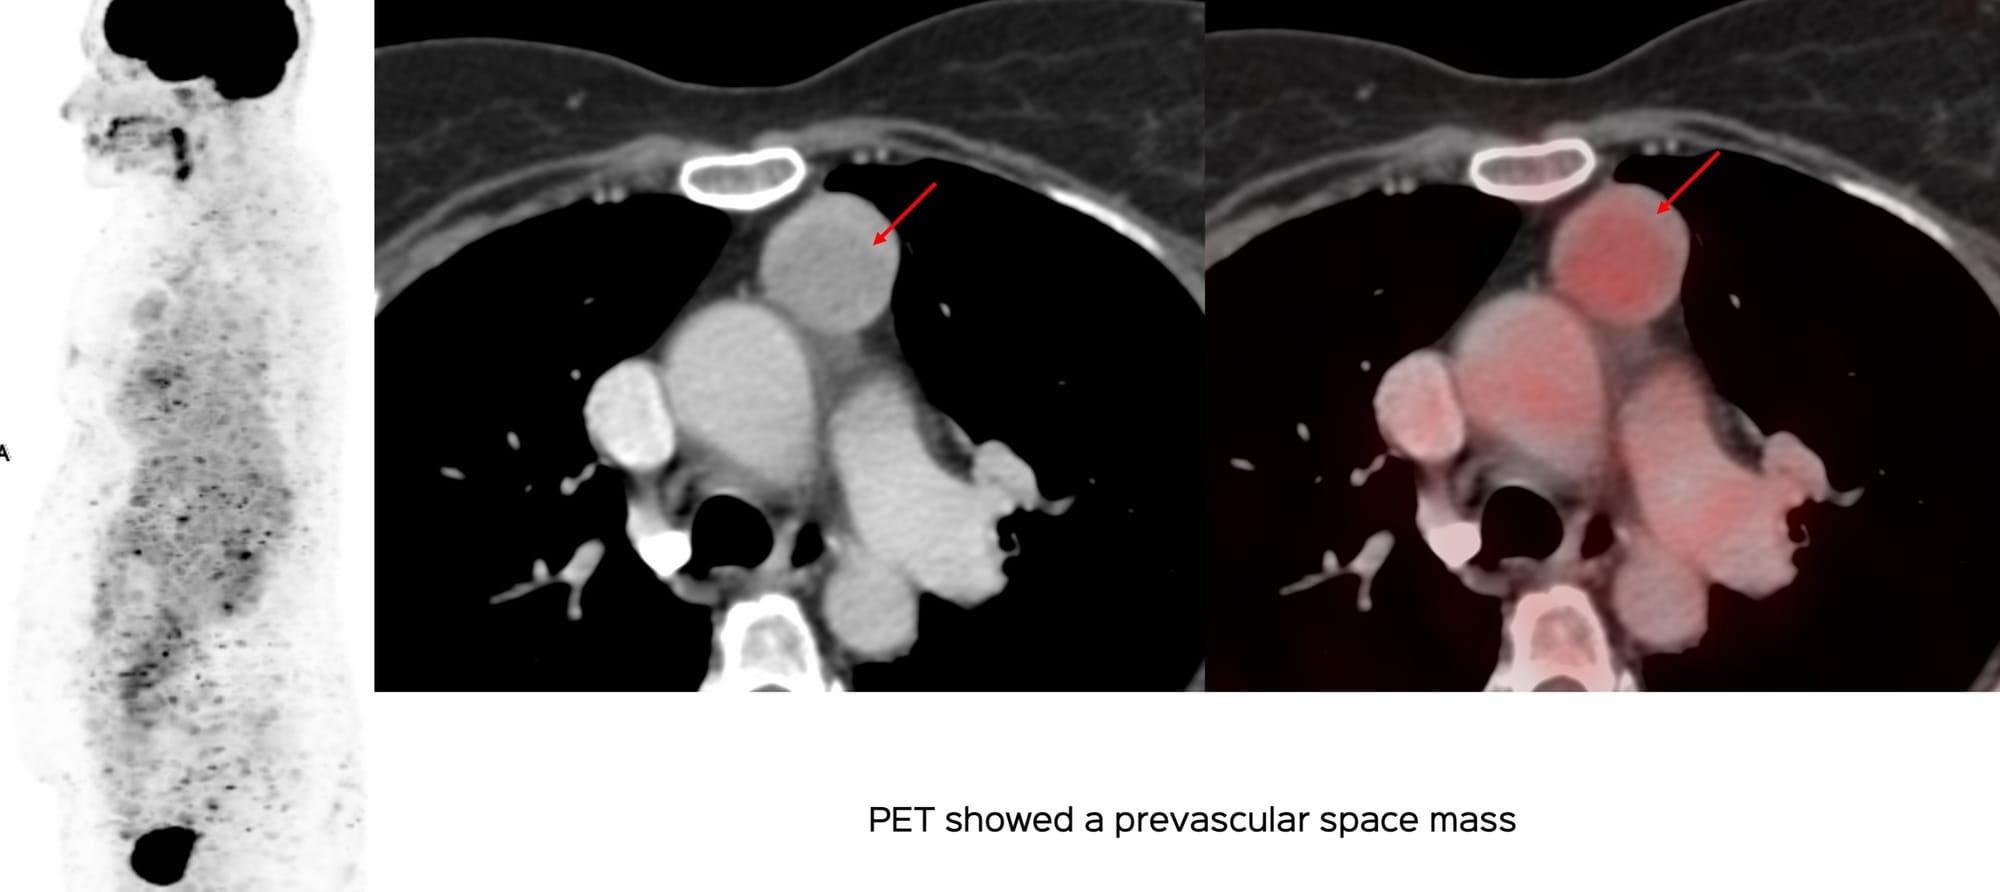

A 56-years old was referred for a CT guided biopsy for a prevascular space mass, with features suggestive of a thymic neoplasm.